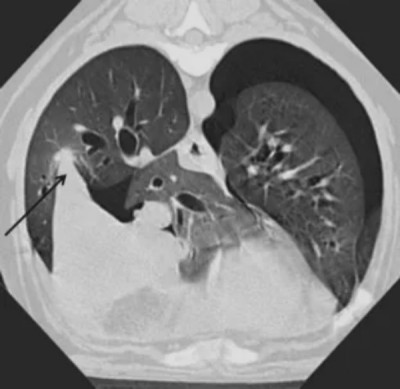

九只犬发生完全肺叶扭转。受累肺叶为:左前叶(5只犬:阿富汗猎犬、俄罗斯猎狼犬、英国斗牛犬、伯恩山犬、巴哥犬),右中叶(2只:杰克罗素梗、比格犬),右前叶(1只:巴哥犬)和左后叶(1只犬:秋田犬)。一只犬(混种犬)在手术中确诊为右中叶部分(180°)扭转。完全肺叶扭转犬的CT表现总结于表1。所有完全肺叶扭转犬均存在胸腔积液。其中6只犬为弥漫性积液,3只犬为病变肺叶周围局灶性积液。所有犬均存在的另一个CT表现是病变肺叶的支气管突然中断。在三只犬中可见支气管扭转(图2)。在一些犬中,支气管在管腔完全闭塞前逐渐变细。另一个常见表现(见于9只犬中的8只)是扭转肺叶的衰减值增加伴肺气肿区域(图3)。受累肺叶在9只犬中的8只增大(图3)。在未受累肺叶中未见任何扭转肺叶中所见的改变。在4只犬中可见移位肺叶中支气管的偏离,在2只犬中支气管受压(图4)。在5只犬中可见受累肺叶位置异常(图5),在1例患者中仅见该肺叶内血管走行异常(在静脉注射造影剂后可见)。三只犬出现气胸(图5),一只犬有纵隔淋巴结病。

图3. 一只8岁杰克罗素梗犬在静脉注射造影剂后,因右中叶扭转的胸部横断计算机断层扫描(CT)图像。该肺叶增大并包含滞留气体(箭头)。心脏轮廓向左移位。右前叶向背侧移位并受压。

图 4. (A) 和 (B): 一只2岁巴哥犬右前叶扭转的胸部背侧重建计算机断层扫描(CT)图像。显示了使用细节算法的螺旋3 mm层厚图像(A)和使用骨算法及边缘增强的高分辨率横断1 mm层厚图像(B)。肺叶增大并包含滞留气体。通向右后叶的支气管移位并围绕增大的前叶弯曲(箭头)。右中叶塌陷并向内侧移位,在此图像上不可见。

图 5. 一只患右中叶扭转的比格犬的横断高分辨率计算机断层扫描(CT)图像。肺叶尖端指向背外侧方向(箭头),表明肺叶移位和旋转。气胸和轻度胸腔积液也可见。